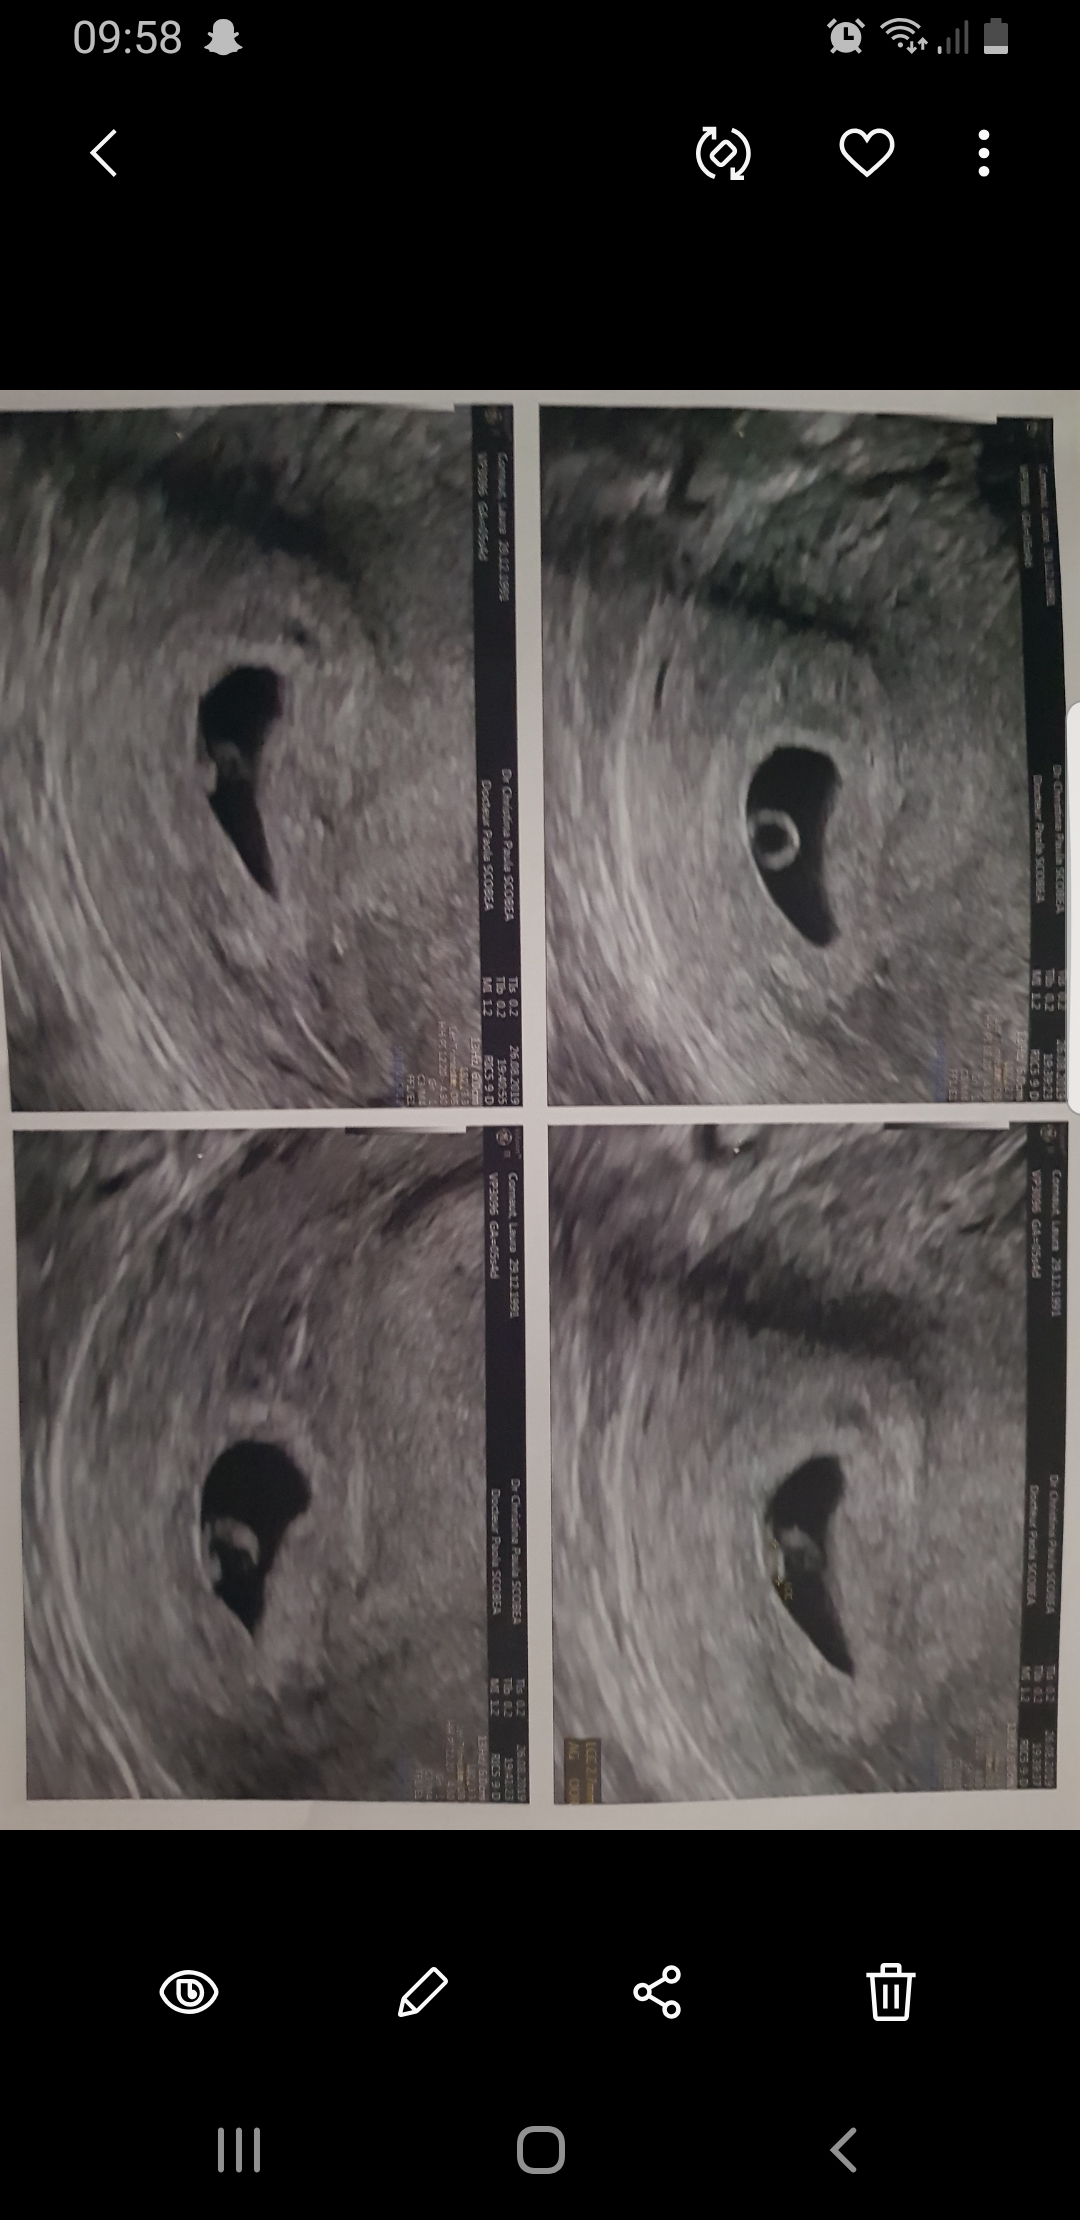

Alors jai eu mon eco comme je tavais dit par ma gynéco. Trop bien embryon de 2.7mm avec un coeur qui bat

Puis 3 jours après. Saignement donc eco de controle a la Pma a 6+1sa. Sac de 20mm, embryon de 3mm coeur qui bat à 118. Pour elle tout est ok. Sauf que depuis je dors plus ni rien.

En 3 jours mon embryon na pas évolué.

Pour la taille, j'avais les mêmes questions que toi. Déjà clairement le fait de faire sur des appareils différents peu jouer, ensuite 3mm à 6sa+1 ne me parait pas du tout choquant de memoire j'etais à 2.9mm à 6sa.

La taille de mon embryon ne me fait pas vraiment peur, car javais penser à toi. Mais cest plus la différence entre les 2 eco.

Je ne connais pas la vitesse de croissance des embryons mais oui le fait que cela ne soit pas le même appareil joue.